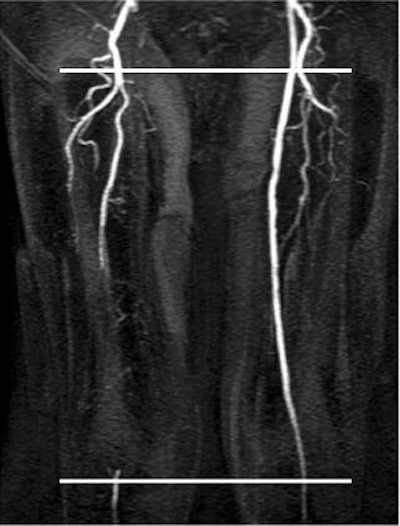

![]() |

| Flow volume curves for right SFA occlusion compared to a left SFA with only mild narrowing. Note in right thigh, loss of triphasic flow and markedly decreased flow volume with SFA occlusion (above). But in the left thigh with only mild SFA disease, triphasic flow is preserved above and below the lesion and there is no peak delay (below). |

The phase contrast data was postprocessed with flow analysis software to obtain flow velocity and flow volume curves above and below the lesion of greatest severity. Two ratios were calculated: